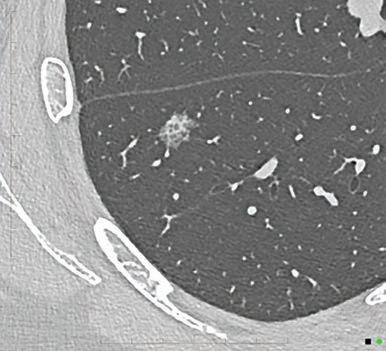

“In the future, every CT will be a photon-counting CT”

Prof. Gabriel Krestin

Erasmus Medical Center Rotterdam, Netherlands

“This will redefine our clinical decision-making right from scan one.”

Prof. Dr. med. Thomas Kröncke University Hospital Augsburg, Germany

“PCD-CT is so exciting because it provides information that existing CT detectors – the types that we’ve used for over 50 years – previously just couldn’t capture.”

Dr. Cynthia McCollough Mayo Clinic CT Clinical Innovation Center. USA

In March 2024 ChestRad introduced Photon Counting CT to Western Australia. But best not to listen to us. Find out what the experts have to say.

At Perth Radiological Clinic your chest imaging investigations are reported locally by WA’s largest team of fellowship trained accredited respiratory radiologists:

• Teaching hospital consultant radiologist appointments. Involved in multidisciplinary team meetings at FSH, MIHC, Mount Hospital, SCGH and JHC.

• RANZCR registered experts in occupational dust lung disease (RANZCR EODLD register).

• Expertise in all types of chest disease including malignancy, ILD, occupational lung diseases, lung cancer, vascular diseases and trauma.

PRC Specialist Chest Radiologist, Dr Stephen Melsom saysIf diagnosed early, particularly before symptoms develop, the progression of chest disease can be slowed

Dr Priority Line 9599 3929 perthradclinic.com.au